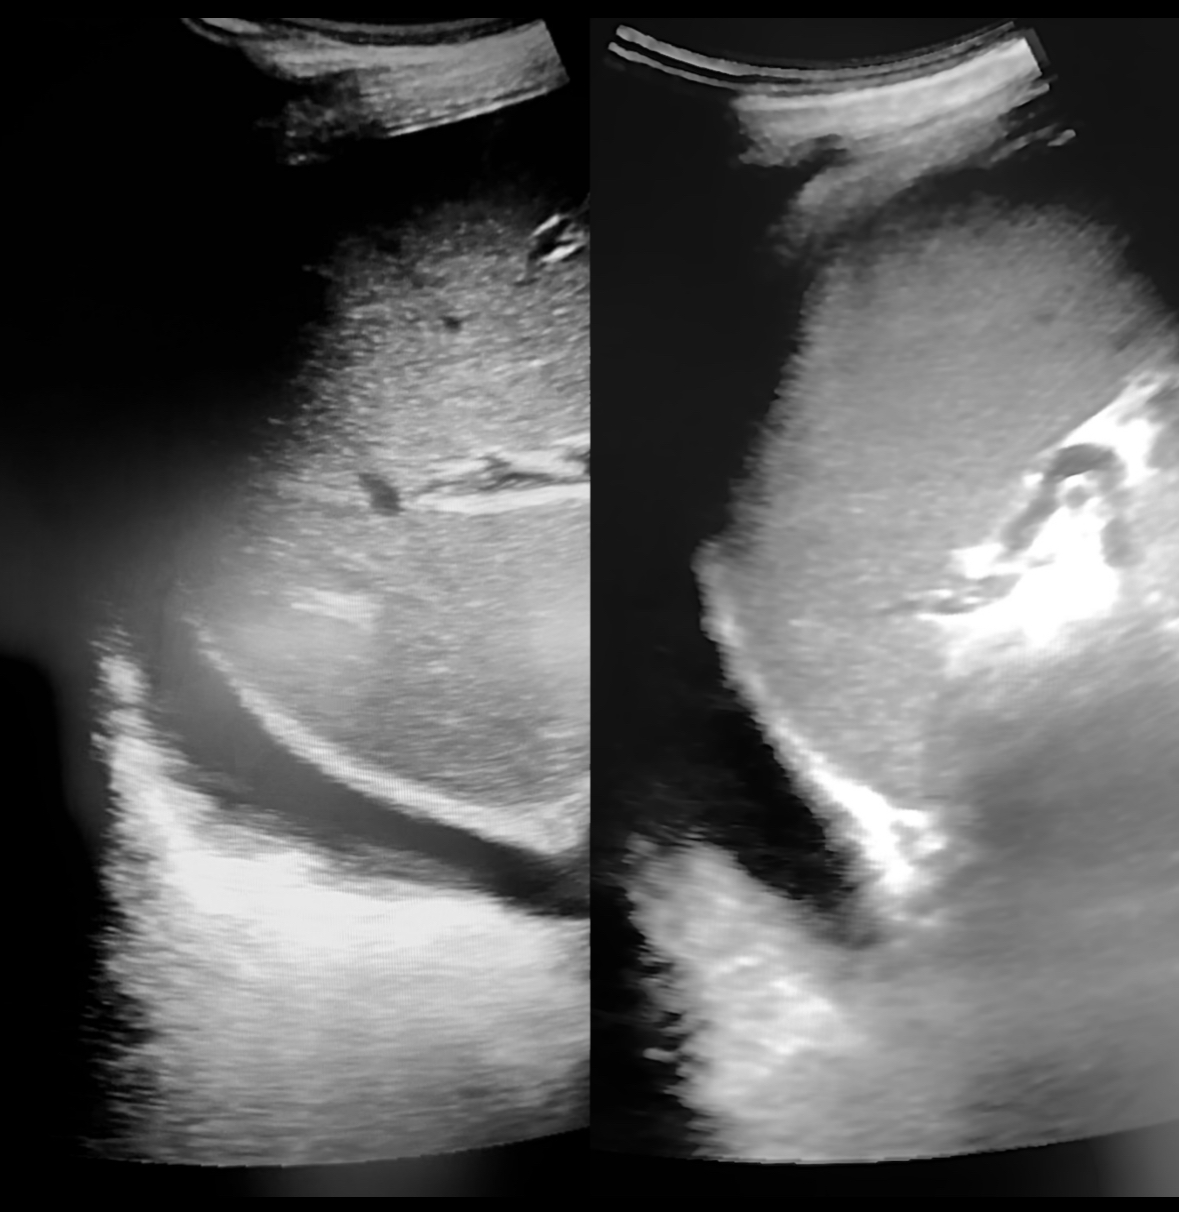

Se decidió realizar ecografía clínica pulmonar apreciándose líneas B en campos 2-4-6 de ambos pulmones con derrame en ambos senos costofrénicos visualizándose la cola de sirena y vena cava congestiva. La ecocardiografía realizada por los cardiólogos no mostró defectos en la contractilidad.